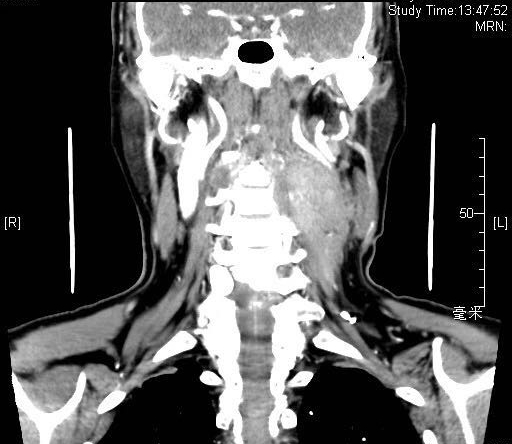

2018年8月患者入院时肿物约7*7cm大小

患者增强CT扫描显示,颈部肿物巨大,向前推压颈总动脉、颈内静脉,颈内静脉部分闭锁,向内侧侵及第1-3颈椎横突